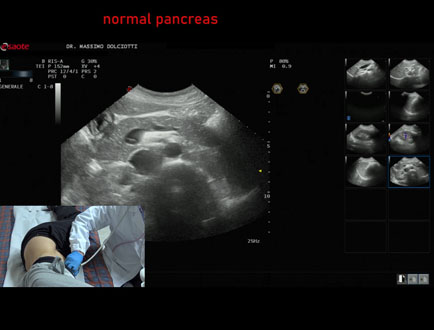

Data inserimento: 05/12/2024

Ecografia del: 28/11/2024

Strumento: Esaote MyLab Eight

Sonda: Convex Multifrequenza 1-8 MHz

Età Paziente: M 20 anni

Motivazione dell'esame: dolori addominali.

Commento all'esame: le immagini ed il video documentano il pancreas di ecostruttura e morfovolumetria regolare, con aspetto ipoecogeno, ben evidenziate la regione cefalica, il corpo e la coda.

Conclusioni: pancreas di ecostruttura e morfovolumetria regolare (pancreas with regular echostructure and morphovolumetry).

Presentazione: Dr. Massimo Dolciotti - Ancona

Elaborazione digitale: Andrea Dini - Ancona